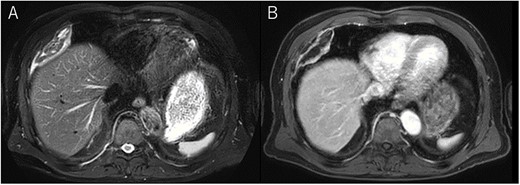

A 72-year-old man with a history of hypertension and left renal cancer (Stage I) was referred to us with a mass in the right chest wall on post-operative follow-up chest computed tomography (CT) for renal cancer. He had a smoking history of 20 pack-years and had no exposure to environmental fumes or dust. Physical examination results were unremarkable. The laboratory findings were within normal limits. Pulmonary function tests and cardiovascular examinations revealed normal results. Chest CT revealed mixed density mass (8.0 × 5.0 × 3.0 cm) located in front of thoracic wall in the third to sixth right intercostal space. The tumor can be revealed as thoracic wall fat (7.8 × 4.8 × 1.2 cm) on CT 1 year before (not considered as abnormal), and it was progressively increased in size and the density changed (Fig. 1A and B). Magnetic resonance imaging (MRI) showed a fatty mass of heterogenic density. T2 high foci (Fig. 2A) and irregular marginal enhancement of the tumor were observed (Fig. 2B). Maximal standard uptake value (SUVmax) of 18F-fluorodeoxyglucose positron emission tomography (FDG-PET) was 3.78 (Fig. 3). Based on these radiological image findings, we scheduled surgery with suspicion of liposarcoma. During the surgery, the patient was placed in the lateral decubitus position. We made 1.5-cm incision in the sixth intercostal space along the posterior axial line for thoracoscopy. We found dense adhesions between the chest wall tumor, lung (front part of all three lobes of the right lung) and diaphragm. We made a 30-cm incision in the fourth intercostal space and resected the tumor along with lung (wedge resection of the front part of all three lobes of the right lung), diaphragm and third to sixth ribs and intercostal muscle. The chest wall defect was 25 × 15 cm and the diaphragm defect was 8 × 5 cm. For reconstruction, the mesh was placed and sutured to the diaphragm and the chest wall. Pathological examination revealed the well-circumscribed tumor with fibrous adhesion between the ribs, lung and diaphragm (Fig. 4A). Microscopically, the tumor consisted of mature fat tissue. There were fat necrosis inflammatory changes in the marginal area of the tumor with foamy macrophages and multinucleated giant cells (Fig. 4B and C). Fluorescence in situ hybridization examination for murine double-minute 2 was negative. Based on these findings, a chest wall lipoma was diagnosed. The post-operative course was uneventful. The patient was followed up for 24 months without evidence of recurrence.

18F-FDG-PET uptake by the tumor; maximum standard uptake value was 3.78.

Several critical radiological image findings have been reported for the differential diagnosis. Lipomas are discrete, encapsulated, homogeneous fatty masses on CT and MRI. On the other hand, thickened or nodular septa (>2 mm), prominent foci of high T2 signal and prominent areas of enhancement on MRI have been reported to be features suspicious of liposarcoma [5, 6]. In addition, tumor size >10 cm and fat content <75% have been reported as radiological features of liposarcoma [6]. SUVmax of FDG-PET reported that lipomas measured 0.8 ± 0.2 and well-differentiated liposarcomas measured 2.3 ± 1.2 [7].

In the present case, tumor enlargement with heterogenic change of the density, thickened septa >2 mm, prominent foci of high T2 signal and prominent areas of enhancement on MRI were seen on preoperative CT and MRI. In addition, the SUVmax of FDG-PET was higher than that of simple lipoma (SUVmax = 3.78). These findings led to a misdiagnosis for liposarcoma. Furthermore, intraoperative findings of dense adhesion between the tumor and surrounding structures strengthen our suspicion of liposarcoma. We could not find another case of intrathoracic lipoma of the chest wall with density change on radiological image and dense adhesion between the surrounding structures.